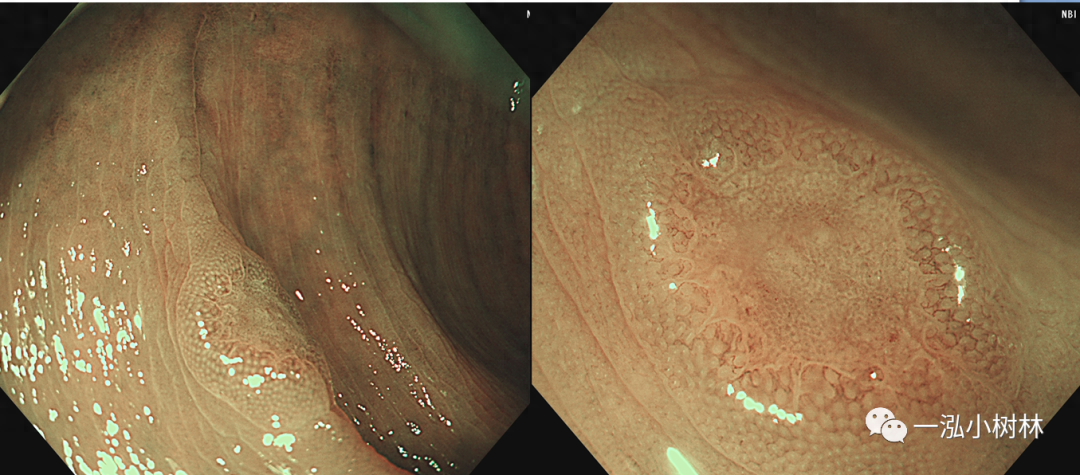

图4 结肠管状腺瘤(Pit Pattern IIIS+IIIL型)